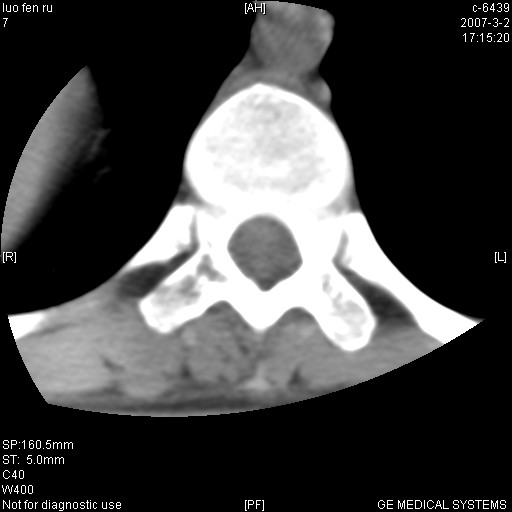

标题: CT6952:T11椎体病变请讨论

女,19岁.背部疼痛一月余.自诉幼时有个外伤史.

腰椎平片示,t11椎体呈楔形改变,椎间隙未见异常.